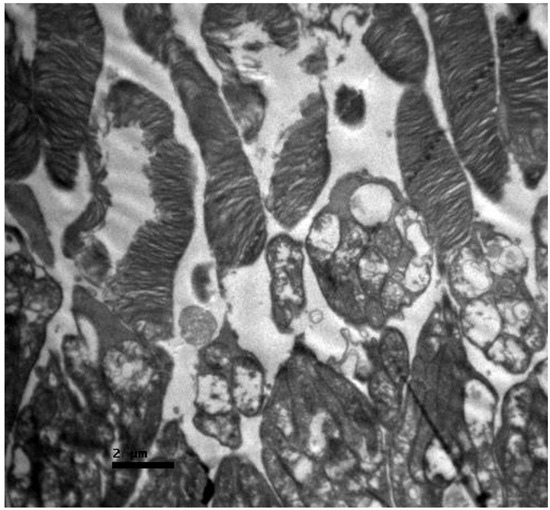

Background/Objectives: Cisplatin is a potent chemotherapeutic agent whose clinical utility is limited by severe side effects, including neurotoxicity affecting the ocular system. The pathophysiology involves oxidative stress and mitochondrial dysfunction, to which the retina is particularly vulnerable. Selenium (Se), an essential trace element and component of antioxidant enzymes, has shown potential in mitigating cisplatin toxicity, although its efficacy with respect to retinal structure and the influence of administration routes remain underexplored. This study aimed to evaluate the protective efficacy of selenium against cisplatin-induced retinal toxicity and compare the effects of intraperitoneal and oral selenium administration. Methods: Forty adult male Wistar rats were randomized into four groups (n = 10 each): Group A (Cisplatin Monotherapy, 3.5 mg/kg IP for 5 days; cumulative dose 17.5 mg/kg); Group B (Cisplatin + Intraperitoneal Selenium, 2.73 mg/kg; cumulative dose 60 mg/kg); Group C (Control); and Group D (Cisplatin + Oral Selenium). Selenium prophylaxis, administered as sodium selenite (Na2SeO3), began two days prior to cisplatin administration and continued for 15 days post-treatment. Retinal evaluation two weeks after cisplatin cessation included light microscopy, semi-quantitative immunohistochemical (IHC) analysis for inflammatory (IL-6) and fibrotic (TGF-β2) markers, and Transmission Electron Microscopy (TEM) for ultrastructural analysis, which were the primary endpoints. Statistical differences in the IHC scores were analyzed via the Kruskal‒Wallis H test with Dunn’s post hoc comparisons. Results: Cisplatin monotherapy (Group A) caused severe disruption of the retinal architecture, including edema, reactive gliosis, and significant upregulation of IL-6 and TGF-β2. Ultrastructural analysis revealed mitochondrial swelling (cristolysis) and photoreceptor disk fragmentation. Intraperitoneal selenium (Group B) was associated with significant structural preservation and intact mitochondria, with TGF-β2 levels comparable to those of the controls, although the IL-6 level remained moderately elevated. Conversely, oral selenium (Group D) suppressed both IL-6 and TGF-β2 expression to near-negative levels but provided less ultrastructural protection, resulting in persistent mitochondrial swelling and focal photoreceptor disruption. Conclusions: Systemic cisplatin induces severe subcellular retinal toxicity characterized by mitochondrial damage and photoreceptor degeneration. Selenium supplementation attenuates these effects; however, outcome patterns differ by administration route. Intraperitoneal selenium was associated with greater morphological and ultrastructural preservation despite persistent IL-6 elevation, whereas oral selenium normalized immunohistochemical marker expression to near-control levels but was associated with more pronounced residual subcellular damage on qualitative TEM assessment. These preliminary morphological and immunohistochemical findings suggest that the route of selenium delivery may influence its neuroprotective profile; however, pharmacokinetic measurements and functional retinal assessments, such as electroretinography, are warranted before its clinical translation. Full article